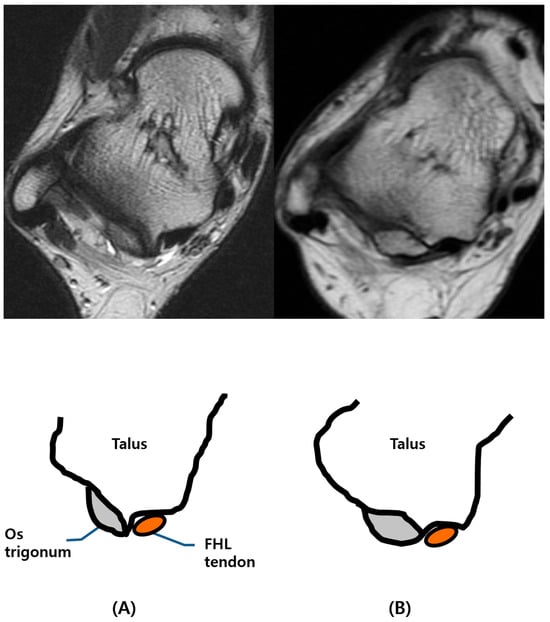

The patients with type II os trigonum had longer transverse diameters of the ossicle (mean value ± SD: 1.21 cm ± 0.41) than type I (0.92 ± 0.36 cm), and there was a significant statistical difference (p = 0.001). There was insufficient evidence to show a difference in the AP diameter of the ossicle (0.83 cm ± 0.19 cm vs. 0.86 ± 0.26 cm; p = 0.387) or the size of the accessory facet (0.41 cm ± 0.31 vs. 0.43 cm ± 0.35, p = 0.419) between type I and type II os trigonum, respectively. These results are depicted graphically in Figure 2.

Figure 2. Dimensions of the os trigonum in each type.